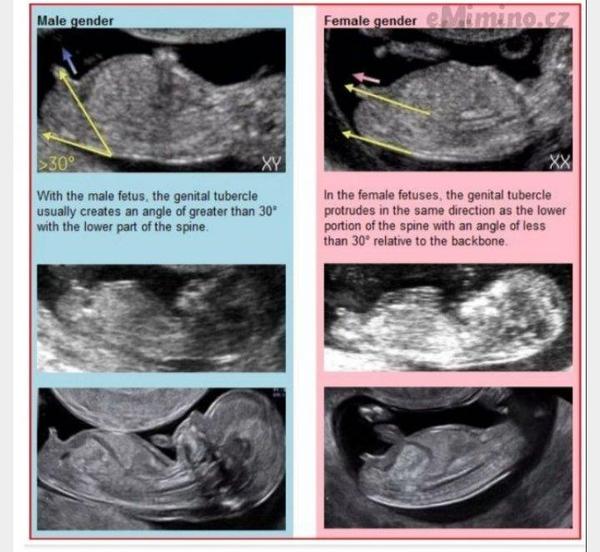

@gbp taky mi to právě přijde "rovné", u nás je ten hrbolek o dost víc nahoru, říkala mi to i doktorka, že právě proto tipuje u nás kluka